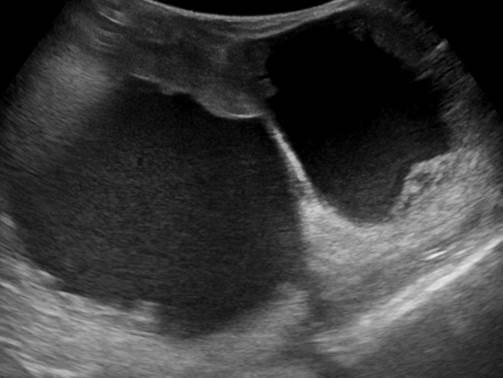

Ung thư vú

Ung thư vú - Ảnh 3

» Thông tin: Nữ giới – 85 tuổi.

» Lâm sàng: Khối tuyến vú.